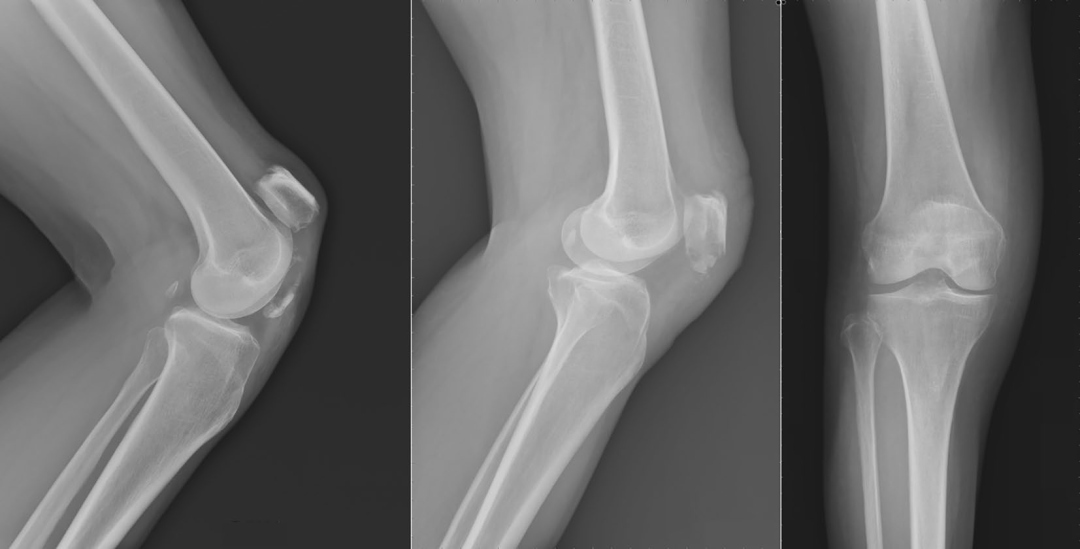

图4. 对照组和实验组患者术后骨折愈合情况比较a-d。患者男,42岁,入院前4 h因跌倒致骨折入院。

a.术前x线侧位片

b.术后x线侧位片

c.术后12周随访x线侧位片。患者女,38岁,入院前3 h因跌倒致骨折入院

d.术前矢状面CT检查

e.术后x线侧位片

f.术后12周随访x线侧位片